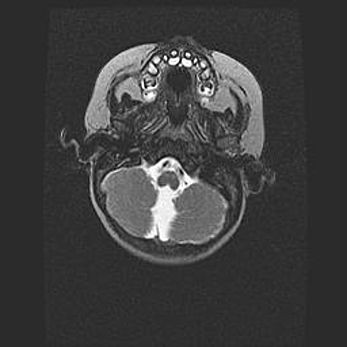

Подострая гематома правой гемисферы мозжечка.

Наружная гидроцефалия.

Возраст: 15 дней

Вес: 3100 г

Пол: женский

Окружность головы: 37 см

Срок гестации: 35-36 недель

При открытой наружной форме гидроцефалии у новорожденных расширяются и переполняются субарахноидные пространства.

Кровоизлияния в мозжечок имеют две клинико-анатомические формы: полушарные гематомы и кровоизлияния в червь.

К появлению этой патологии может привести: повреждения головного мозга, возникающие в результате асфиксии и гипоксии плода при беременности, или травмы во время родов. Редко гематома мозжечка может быть результатом первичной коагулопатии и сосудистой мальформации, диссеминированном внутрисосудистом свертывании, изоиммунной тромбоцитопении.